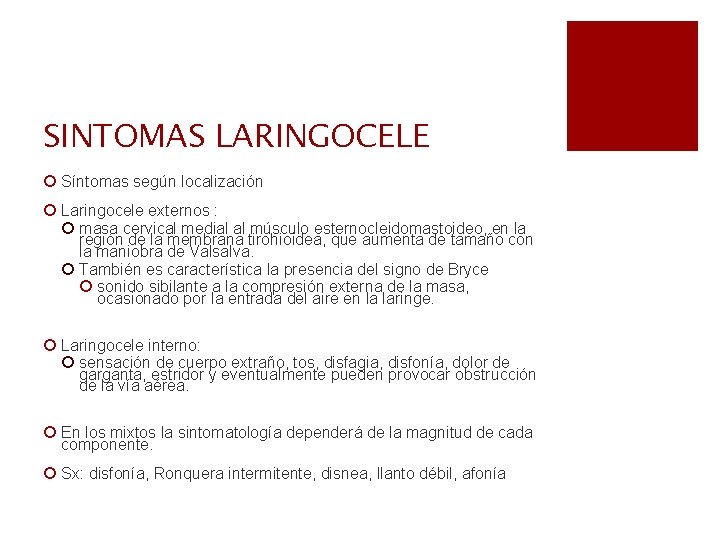

SINTOMAS LARINGOCELE ¡ Síntomas según localización ¡ Laringocele externos : ¡ masa cervical medial al músculo esternocleidomastoideo, en la región de la membrana tirohioidea, que aumenta de tamaño con la maniobra de Valsalva. ¡ También es característica la presencia del signo de Bryce ¡ sonido sibilante a la compresión externa de la masa, ocasionado por la entrada del aire en la laringe. ¡ Laringocele interno: ¡ sensación de cuerpo extraño, tos, disfagia, disfonía, dolor de garganta, estridor y eventualmente pueden provocar obstrucción de la vía aérea. ¡ En los mixtos la sintomatología dependerá de la magnitud de cada componente. ¡ Sx: disfonía, Ronquera intermitente, disnea, llanto débil, afonía